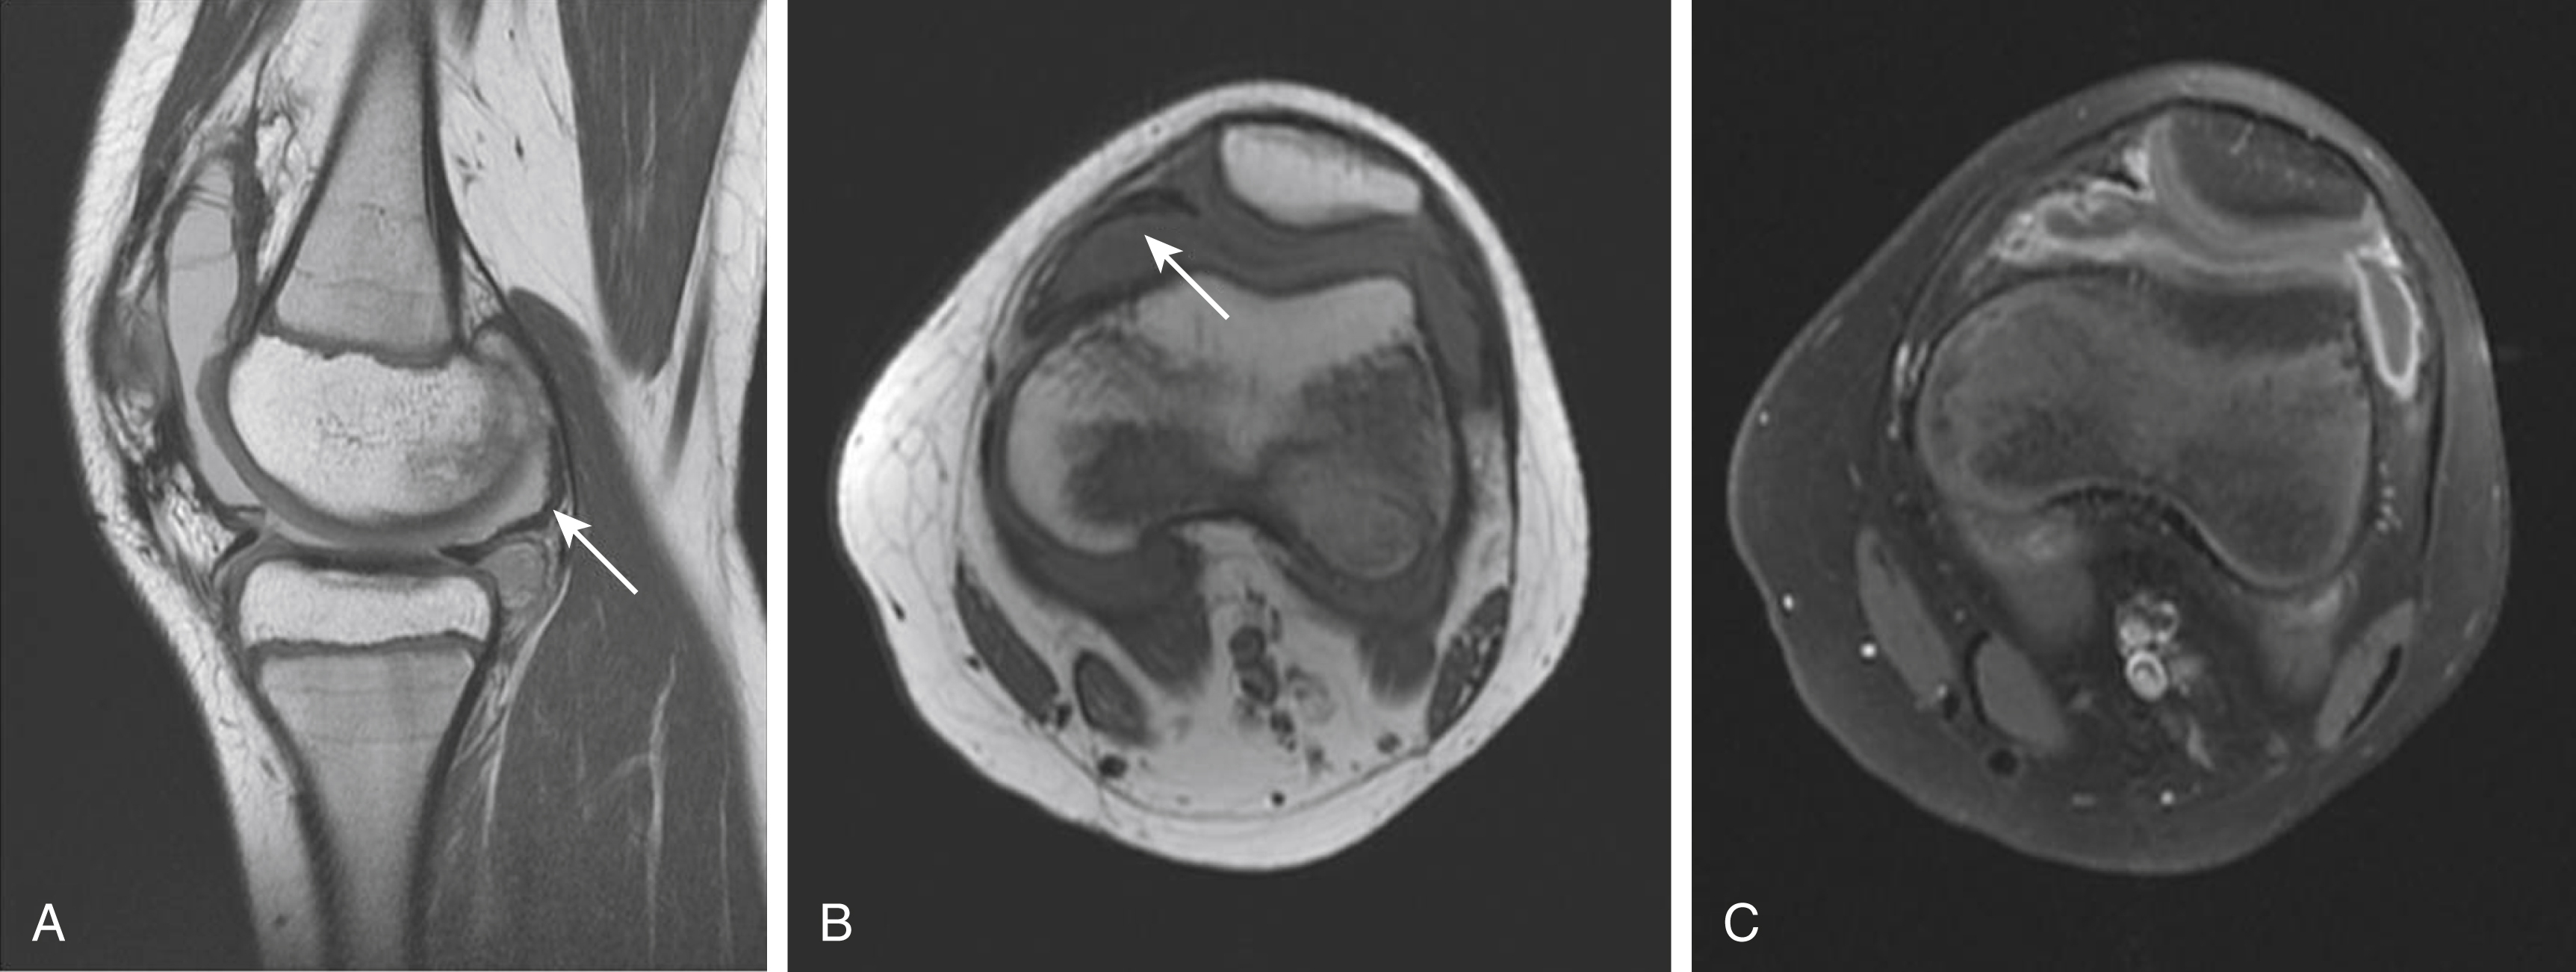

The difficulty in assessing some of these areas with arthroscopy (especially posteromedian synovial joint recess) highlights the importance of assessment with MRI. Findings of PVNS on MRI includes an irregularly thickened or frondlike T1- and T2-hypointense synovium (caused by hemosiderin deposition) ( Fig. 16.3 ). The resulting low signal intensity is exaggerated by signal loss or blooming with gradient-echo or susceptibility-weighted sequences. Despite hypointensity on T2-weighted imaging, PVNS may appear hyperintense on Short Tau Inversion Recovery (STIR) imaging. Avid enhancement after gadolinium is the norm. PVNS may be associated with joint effusions or multiseptated popliteal cyst. Bone involvement (e.g., edema, erosion) is rare in children. Although radiographs may detect any bone involvement and US may detect a large soft tissue mass and reactive effusion, the finer details, anatomy, and characterization of the articular lesions are best delineated with MRI.

Fig. 16.3, Ten-year-old with history of knee swelling and pain with sagittal proton density sequence (A) and axial T1-weighted sequence (B) demonstrating hypointense signal of synovium and the Hoffa fat pad ( arrows ), with axial postcontrast fat-saturated image (C) demonstrating enhancing thickened synovium consistent with pigmented villonodular synovitis.

Histologically, PVNS is characterized by synovial cell hyperplasia; accumulation of giant cells, macrophages, and fibroblasts; and intracellular and extracellular hemosiderin deposition. Treatment for PVNS is synovectomy. Recurrence for PVNS is estimated to be around 20% to 40%, highlighting the use of MRI in postoperative evaluation as well.